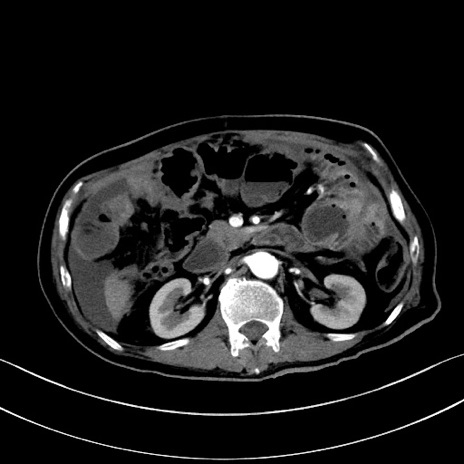

冠状断像

【症例】60歳代男性

【現病歴】胃癌にて胃全摘後。食思不振が悪化し、夜中に嘔吐することがある。

【既往歴】胃癌、胃全摘、脾摘、胆摘後

【データ】WBC 5900、CRP 10.56